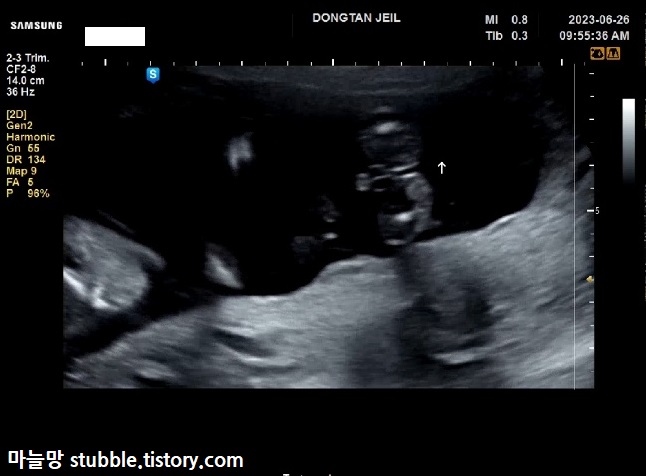

이건 제가 캡쳐 해놓고도 한참을 이게 뭔가 하고 봤네요.

구순열 여부를 살짝만 (맛보기로) 본 것 같아요. 자세한 건 정밀초음파를 봐야 알겠지만요.

화면 나오자마자 정면에서 너무 또렷하게 보여서 신랑이 먼저 「보이네요!」라고 말했고, 담당쌤 웃으시고 아무 말하지 않으셨어요.

아들맘 확정입니다.